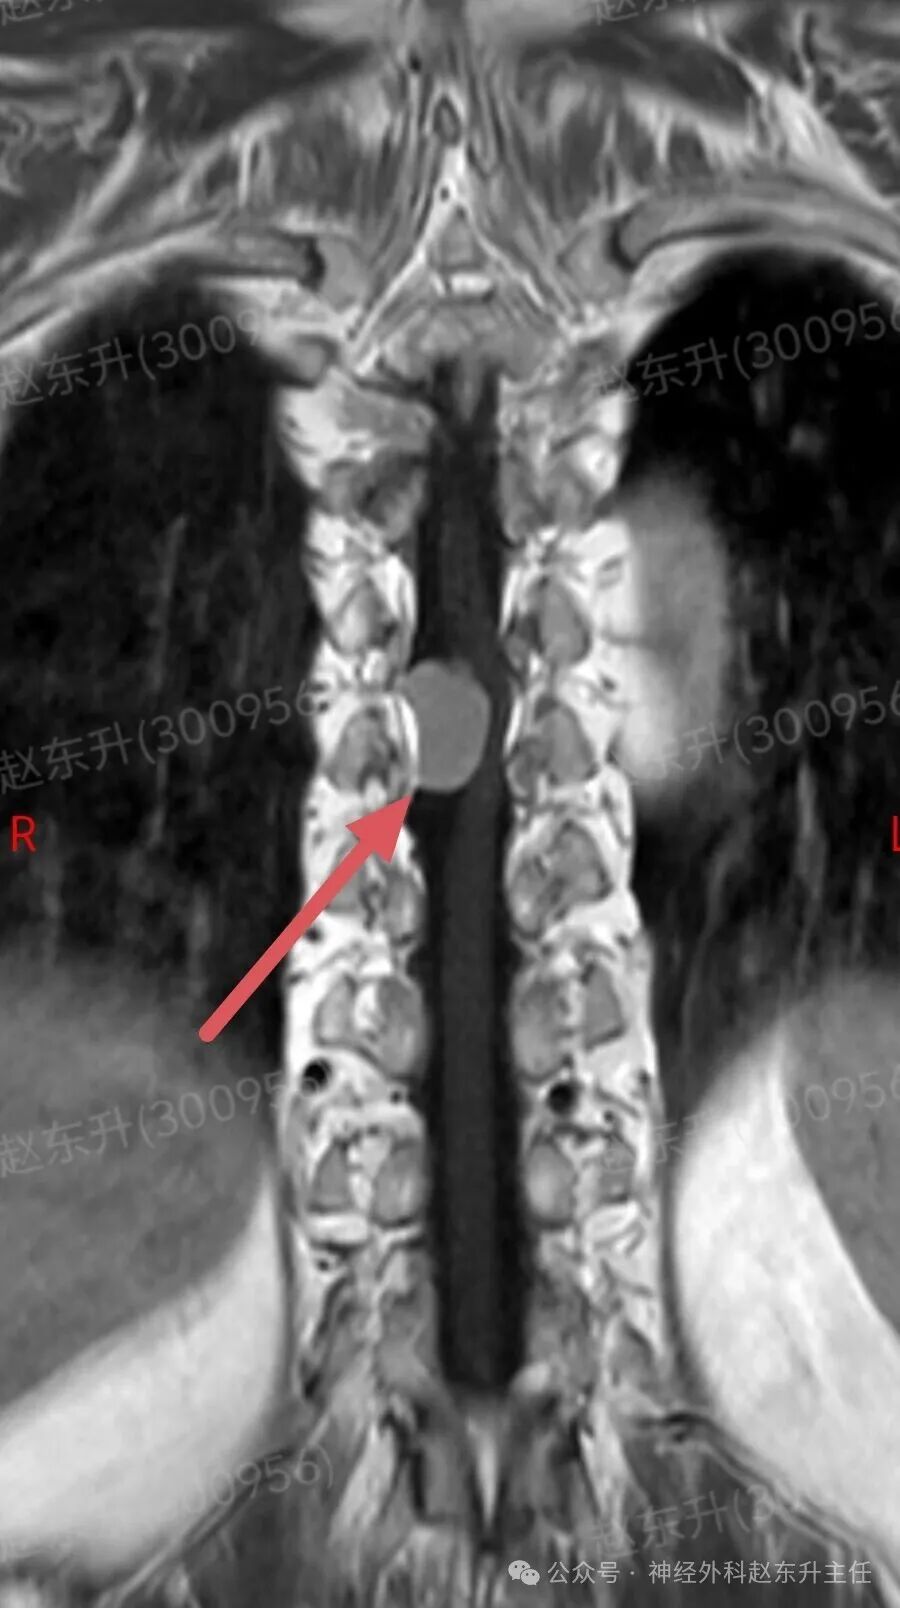

今天介绍一个58岁女性患者,因为腰部疼痛麻木伴双下肢麻木乏力半年入院的患者半年前开始出现下肢麻木乏力,但可独立行走。没有引起重视,逐渐症状加重,伴有腰部疼痛,夜间疼痛比较明显明显难以忍受,随后在当地医院查了ct和核磁共振发现椎管内一个巨大的肿瘤压迫脊髓。当地医院不敢手术,因为患者虽然疼痛麻木,疼痛评分有10分,但可以行走。随后他到西安市红会医院神经外科找到了赵东升主任,经过详细的术前评估和检查以后在全麻下显微镜下进行了肿瘤全切术后患者疼痛立即减轻,术后第2天开始做经颅磁刺激等神经康复治疗。术后一周就可以下地行走了,大小便也恢复了正常。患者感激到终于有人帮我解决了这个折磨他半年的一个疾病。

磁共振成像:是首选和确诊性检查。典型表现:T1加权像呈等或稍低信号,T2加权像呈等或稍高信号;增强扫描后呈现均匀、显著的强化,可见特征性的“硬膜尾征”(邻近硬脊膜线状强化)。